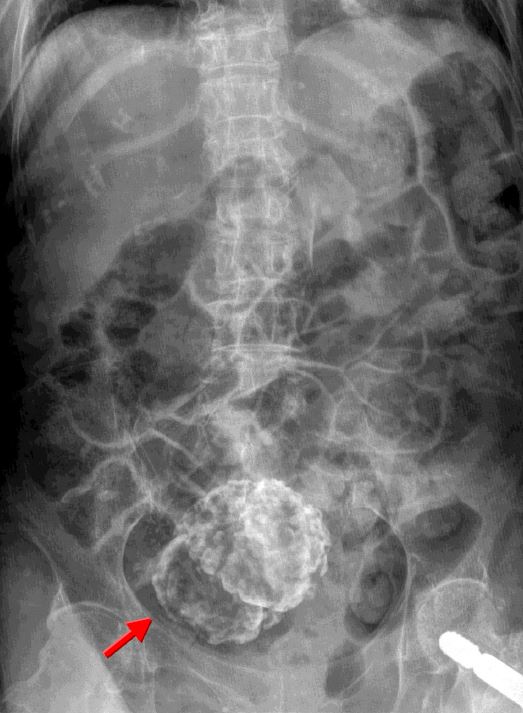

A. TB with autonephrectomy

B.Calcified RCC

C.Staghorn stones

D.Porcelain gallbladder